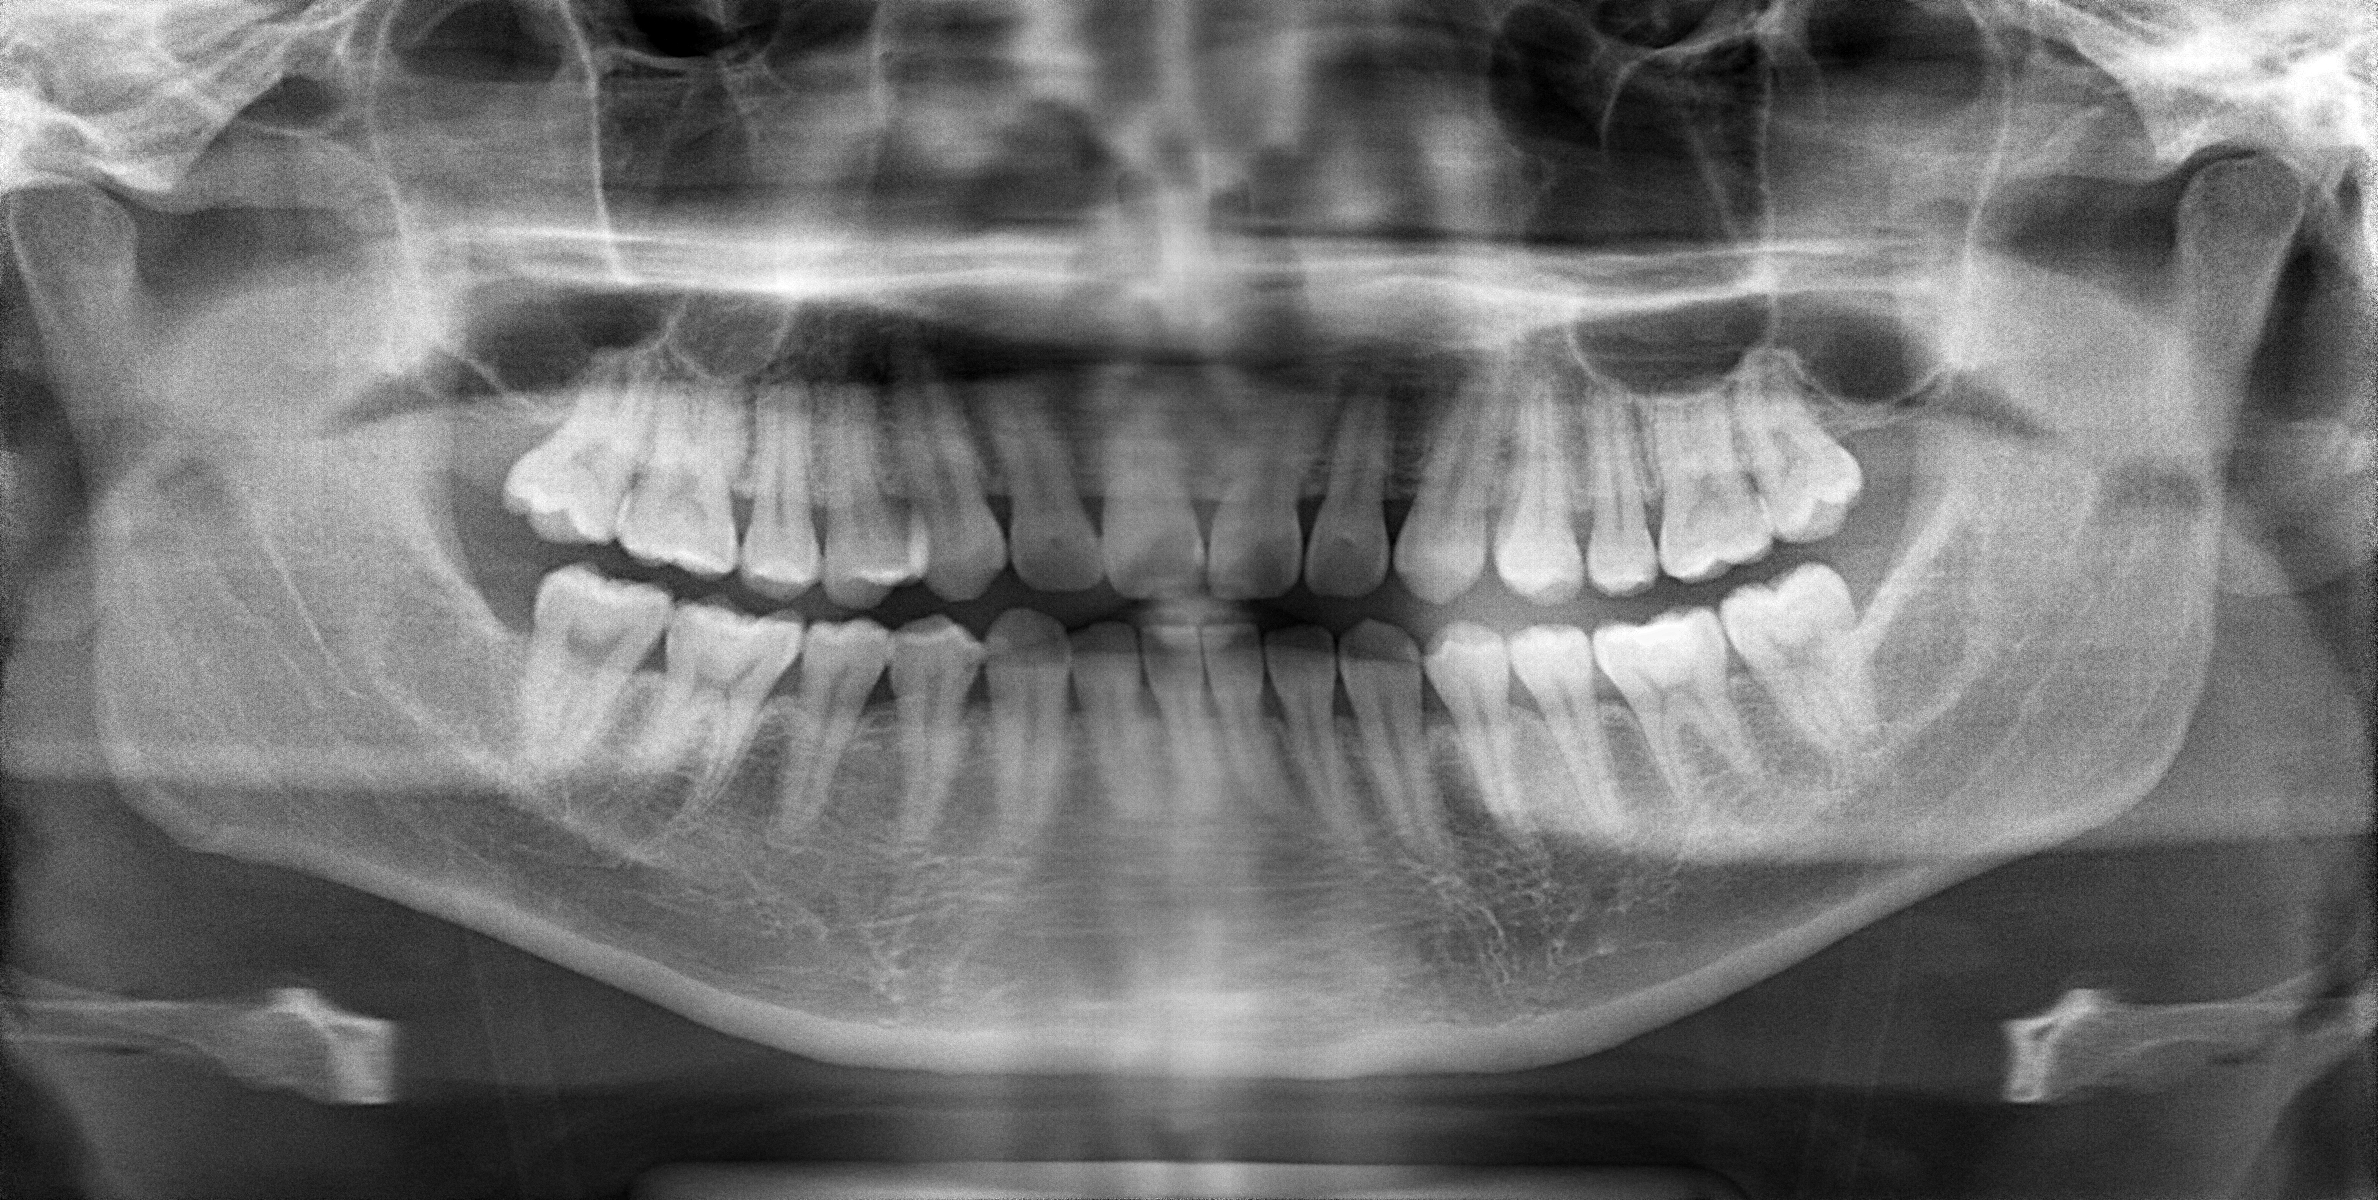

パノラマレントゲン写真ですが、ご覧のおり歯そのものには特に問題ありません。それどころかこの患者さんは素晴らしい歯とお口をしています。全ての歯の神経が残っているんですね。大体、歯医者さんに来る患者さん何処かしら歯の神経を取ってあります。そして健康な歯と歯ぐきも保っている、とてもデンタルIQの高い患者さんということがわかります。

ただし顎の骨に左右差があり、高さがちょっと違います。これも噛み合わせ不調の原因の一つとなっています。